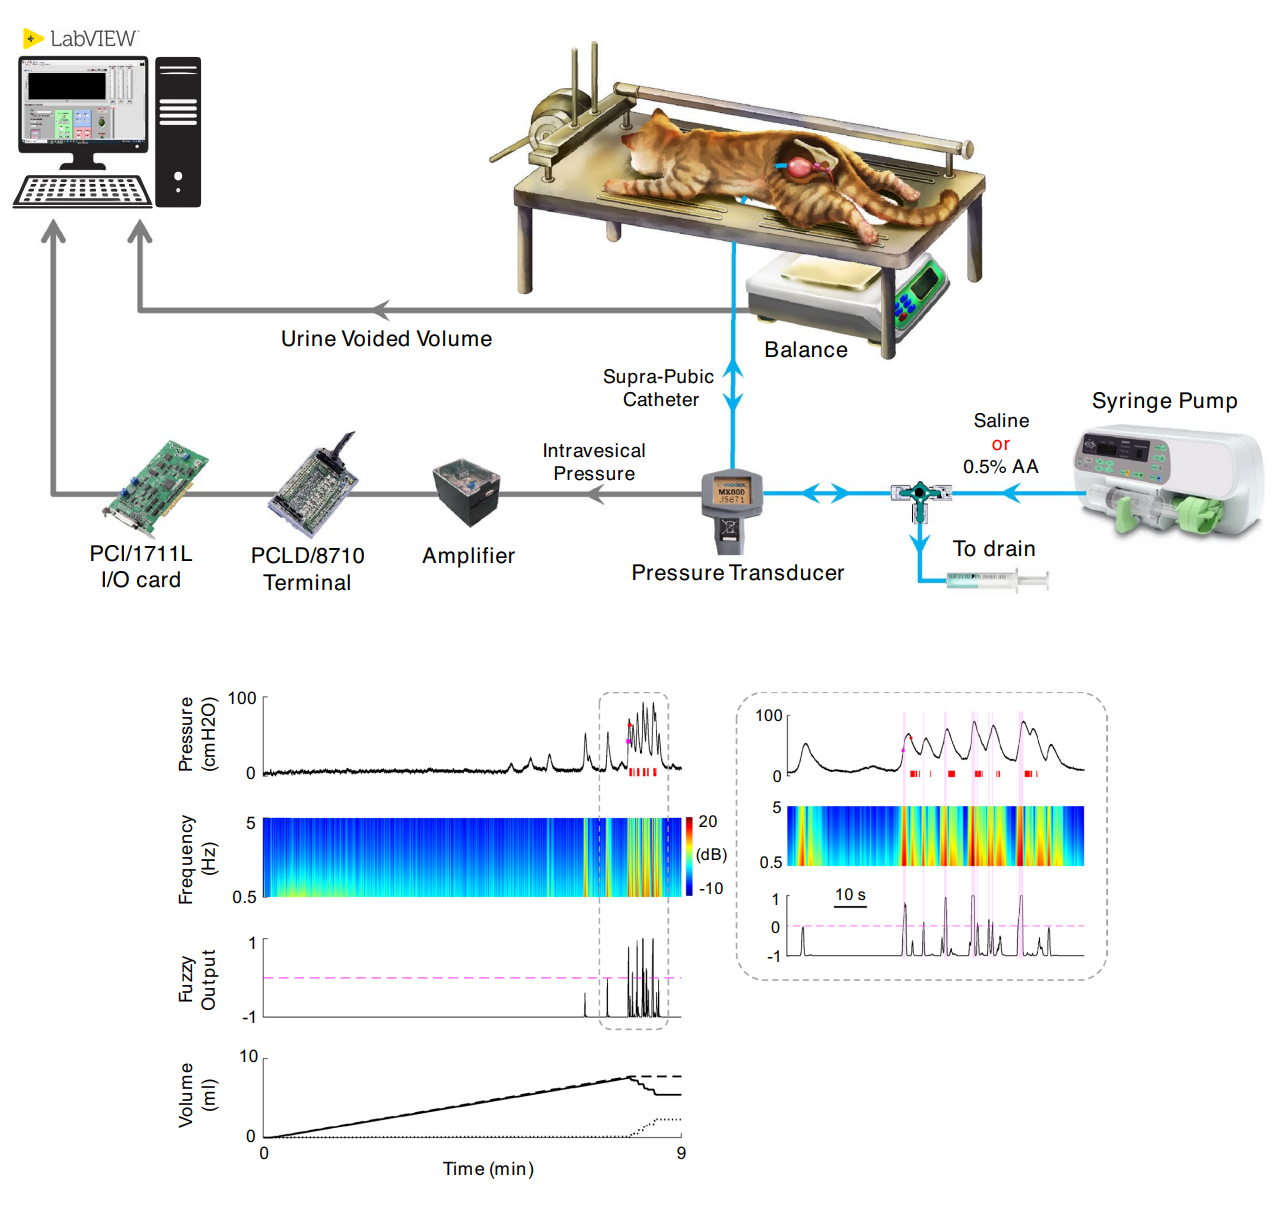

کنترل عملکرد مثانه

کنترل عملکرد مثانه با تحریک الکتریکی یک روش نوآورانه برای کمک به افرادی است که به دلیل آسیبهای نخاعی یا اختلالات عصبی توانایی کنترل مثانه خود را از دست دادهاند. این تکنیک با استفاده از الکترودهایی که به اعصاب کنترلکننده عملکرد مثانه مانند عصب پودندال، پلویک، ریشه ساکرال و ناحیه ساکرال نخاع متصل میشوند، سیگنالهای الکتریکی را برای تحریک این اعصاب ارسال میکند. این تحریک باعث میشود که مثانه به درستی منقبض یا شل شود و به بیماران اجازه میدهد تا دفع ادرار را بهتر کنترل کنند.این روش درمانی برای افرادی که دچار بیاختیاری ادرار یا احتباس ادرار شدهاند، بسیار مفید است. به عنوان مثال، بیمارانی که پس از آسیبهای نخاعی قادر به تخلیه کامل مثانه نیستند، میتوانند با استفاده از تحریک الکتریکی عصبی، عضلات مثانه خود را فعال کرده و جریان طبیعی ادرار را برقرار کنند. این تکنیک همچنین به بهبود کیفیت زندگی افرادی که دچار اختلالات مثانه هستند کمک کرده و در بسیاری از موارد میتواند جایگزین کاتترهای دائمی یا جراحیهای تهاجمی شود.

4. Qasemi, A., Aminian, A., & Erfanian, A. (2024). Real-time prediction of bladder urine leakage using fuzzy inference system and dual Kalman filtering in cats. Scientific Reports, 14(1), 3879.